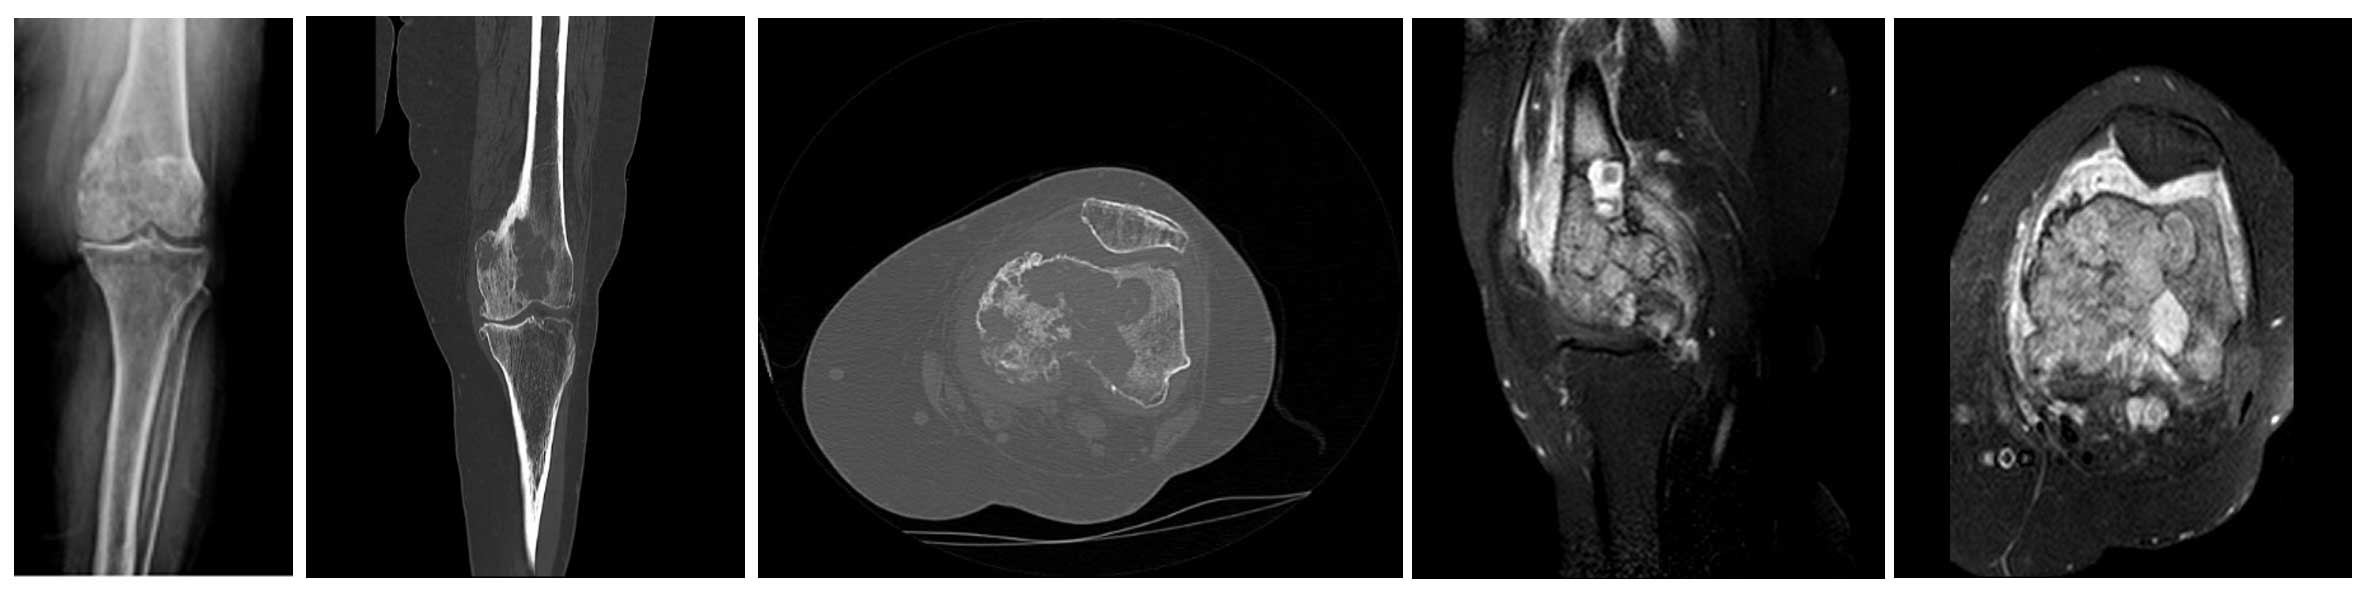

Vaka 44: Akciğer Kanseri Sol Uyluk (Femur) Alt Uç Metastazı

Ameliyat Öncesi: Röntgen ve tomografi kesitlerinde metastaza bağlı yeniklikler ve ciddi harabiyet, MR’da uyluk kemiği alt kısmını dolduran ve kemiğin dışına taşan tümör dokusuna eşlik eden çevreleyen ödem görünmekte.